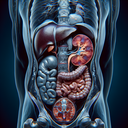

Магнітно-резонансна томографія (МРТ) органів черевної порожнини – це неінвазивний метод діагностики, який використовує магнітні поля і радіохвилі для створення детальних зображень внутрішніх органів. МРТ допомагає отримати чітке уявлення про структуру і стан органів без використання рентгенівських променів. ### Коли проводять МРТ черевної порожнини: - **Детекція патологій печінки, селезінки, підшлункової залози, нирок, жовчного міхура...

МРТ печінки — це неінвазивний метод візуалізації, який використовується для детального обстеження структури та функції печінки. Ось коли і навіщо може знадобитися ця процедура: ### Коли звертатися до МРТ печінки: 1. **Підозра на пухлини**: Виявлення доброякісних або злоякісних утворень...

МРТ селезінки (магнітно-резонансна томографія) – це неінвазивний метод візуалізації, який використовують для детального обстеження цього органу. МРТ дозволяє отримати точні зображення тканин без використання рентгенівського випромінювання. **Коли проводять МРТ селезінки:** 1...

МРТ підшлункової залози - це діагностичний метод, що використовує магнітне поле і радіохвилі для отримання детальних зображень підшлункової залози. Його застосовують для оцінки структури та функції залози. **Коли призначають МРТ підшлункової залози:** 1...